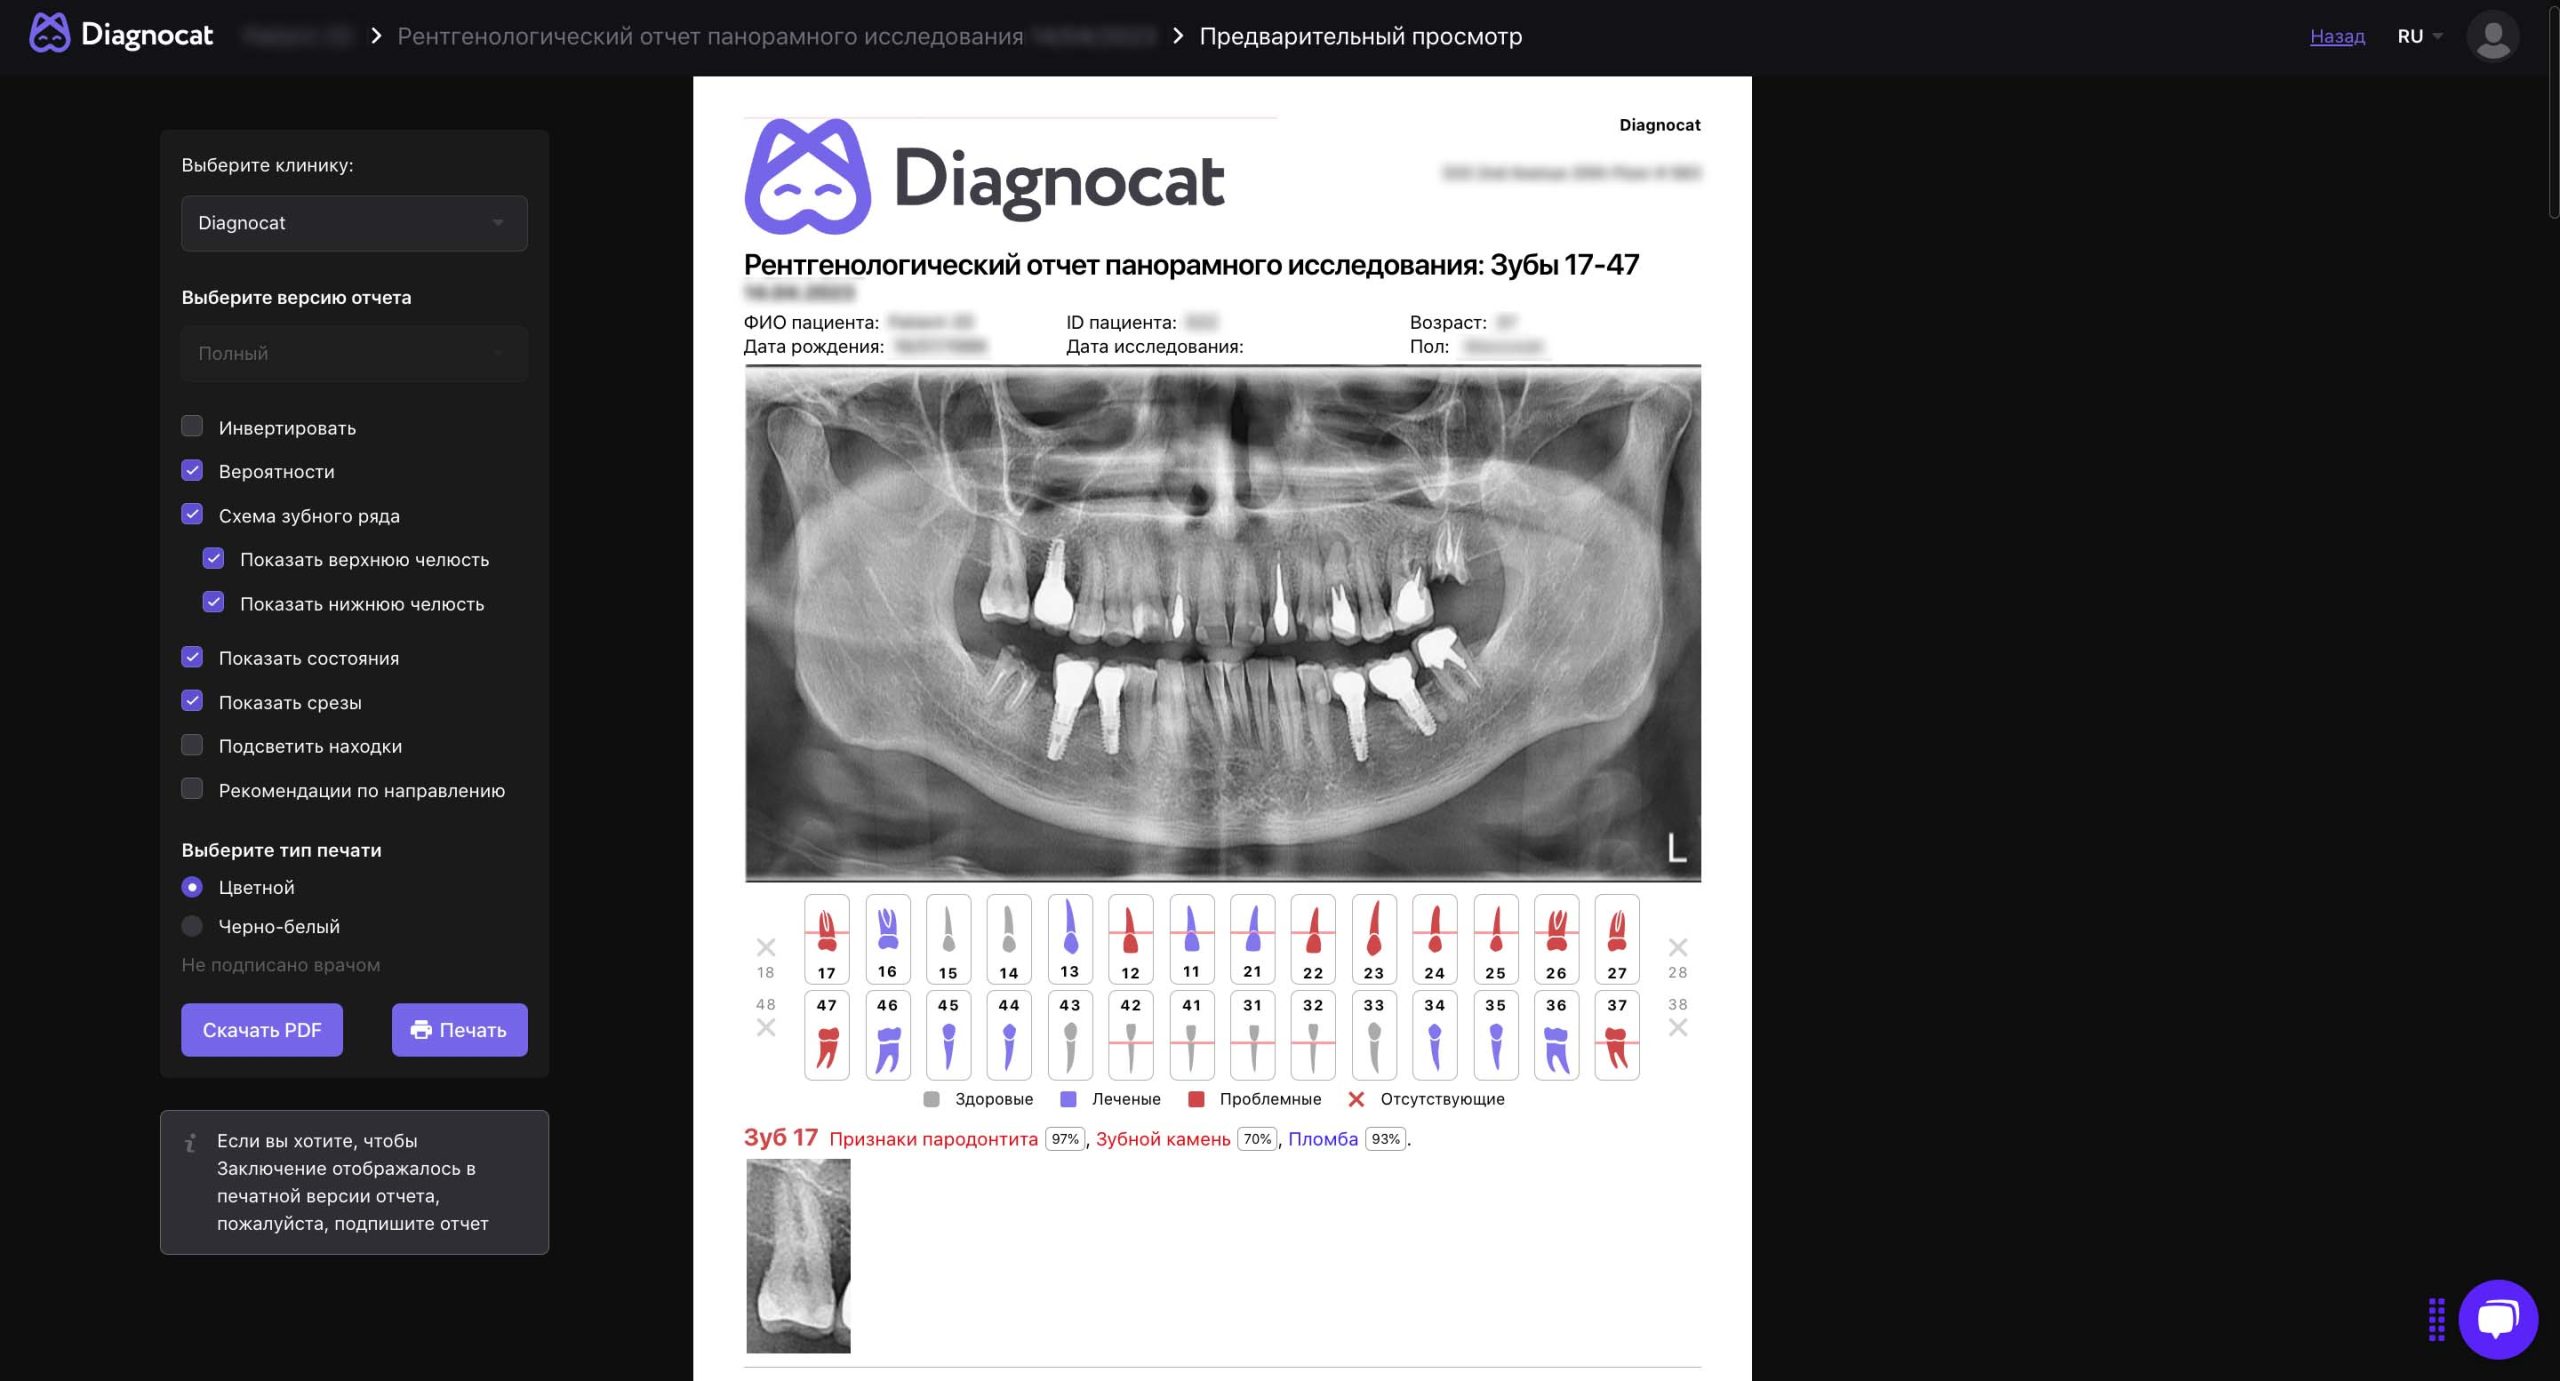

На основе загруженного панорамного снимка алгоритм генерирует отчет с диагностическими находками, которые обнаружил искусственный интеллект.

Diagnocat дает возможность сохранять рентгенологические отчеты в PDF-формате и распечатывать их. Зубы, требующие лечения, выделены в отчете красным цветом. Отчёт дополняет план лечения и позволяет показывать пациентам связь между клиническим состоянием их зубов и необходимым медицинским вмешательством.

Форма с цветовой кодировкой: здоровые, больные и ранее пролеченные зубы

Следующий этап — подготовка отчета с перечнем выявленных состояний. Он представляет собой форму с описанием каждого зуба. Отчет формируется в формате PDF — его сразу можно распечатать. Зубы, требующие врачебного вмешательства, выделяются красным цветом — это особенно удобно при разговоре с пациентом. Отчет дополняет план лечения: пациенту можно наглядно показать взаимосвязь между его состоянием ЧЛО и необходимым лечением.

Отчет с готовым стоматологическим заключением по каждому зубу формируется в несколько кликов. Сюда входят патологии и состояния, обозначенные на стоматологической карте определенными цветами.

Форма с цветовой кодировкой: показаны здоровые, ранее пролеченные, отсутствующие и подверженные заболеваниям зубы

Фиксация более чем 65 состояний, включая аномалии верхнечелюстных синусов и костной структуры, периапикальные поражения, убыль костной ткани при заболеваниях пародонта, признаки кариеса, ретенированные зубы и результаты предыдущего эндодонтического лечения